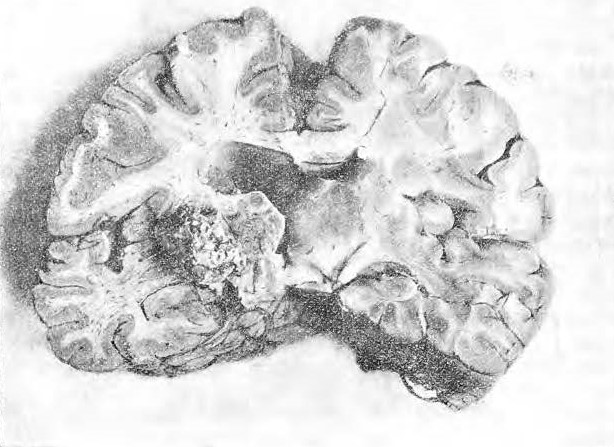

Мозговыя оболочки не представляютъ ничего особеннаго. Вены мягкой мозговой оболочки слегка расширены. Извилины мозга нормальной конфигураціи. При проведеніи фронтальнаго разрѣза въ области центральной доли ножъ въ области полосатаго тѣла наткнулся на твердое тѣло, занимавшее большую часть nuclei lentiformis et caps. int d. и простирающееся кнаружи въ бѣлое вещество до коры insulae Reilii и книзу почти до согни inf. ventriculi lateralis. Описанное твердое тѣло повсюду внѣдрено въ мозговое вещество, изъ котораго оно не выдѣляется. Его поверхность покрыта выступами и зазубринами. Продольный размѣръ его 2,3 сант.; поперечный почти 2 сант. См. рис. 1.

На поверхности lobi semilunaris post. s. и 1. cuneiform, d. находится также подъ мягкой мозговой оболочкой маленькая костная опухоль длиною въ 0,5 пр. 0,6 сант., проникающая въ вещество мозга.

Рис.1

Рис. 2